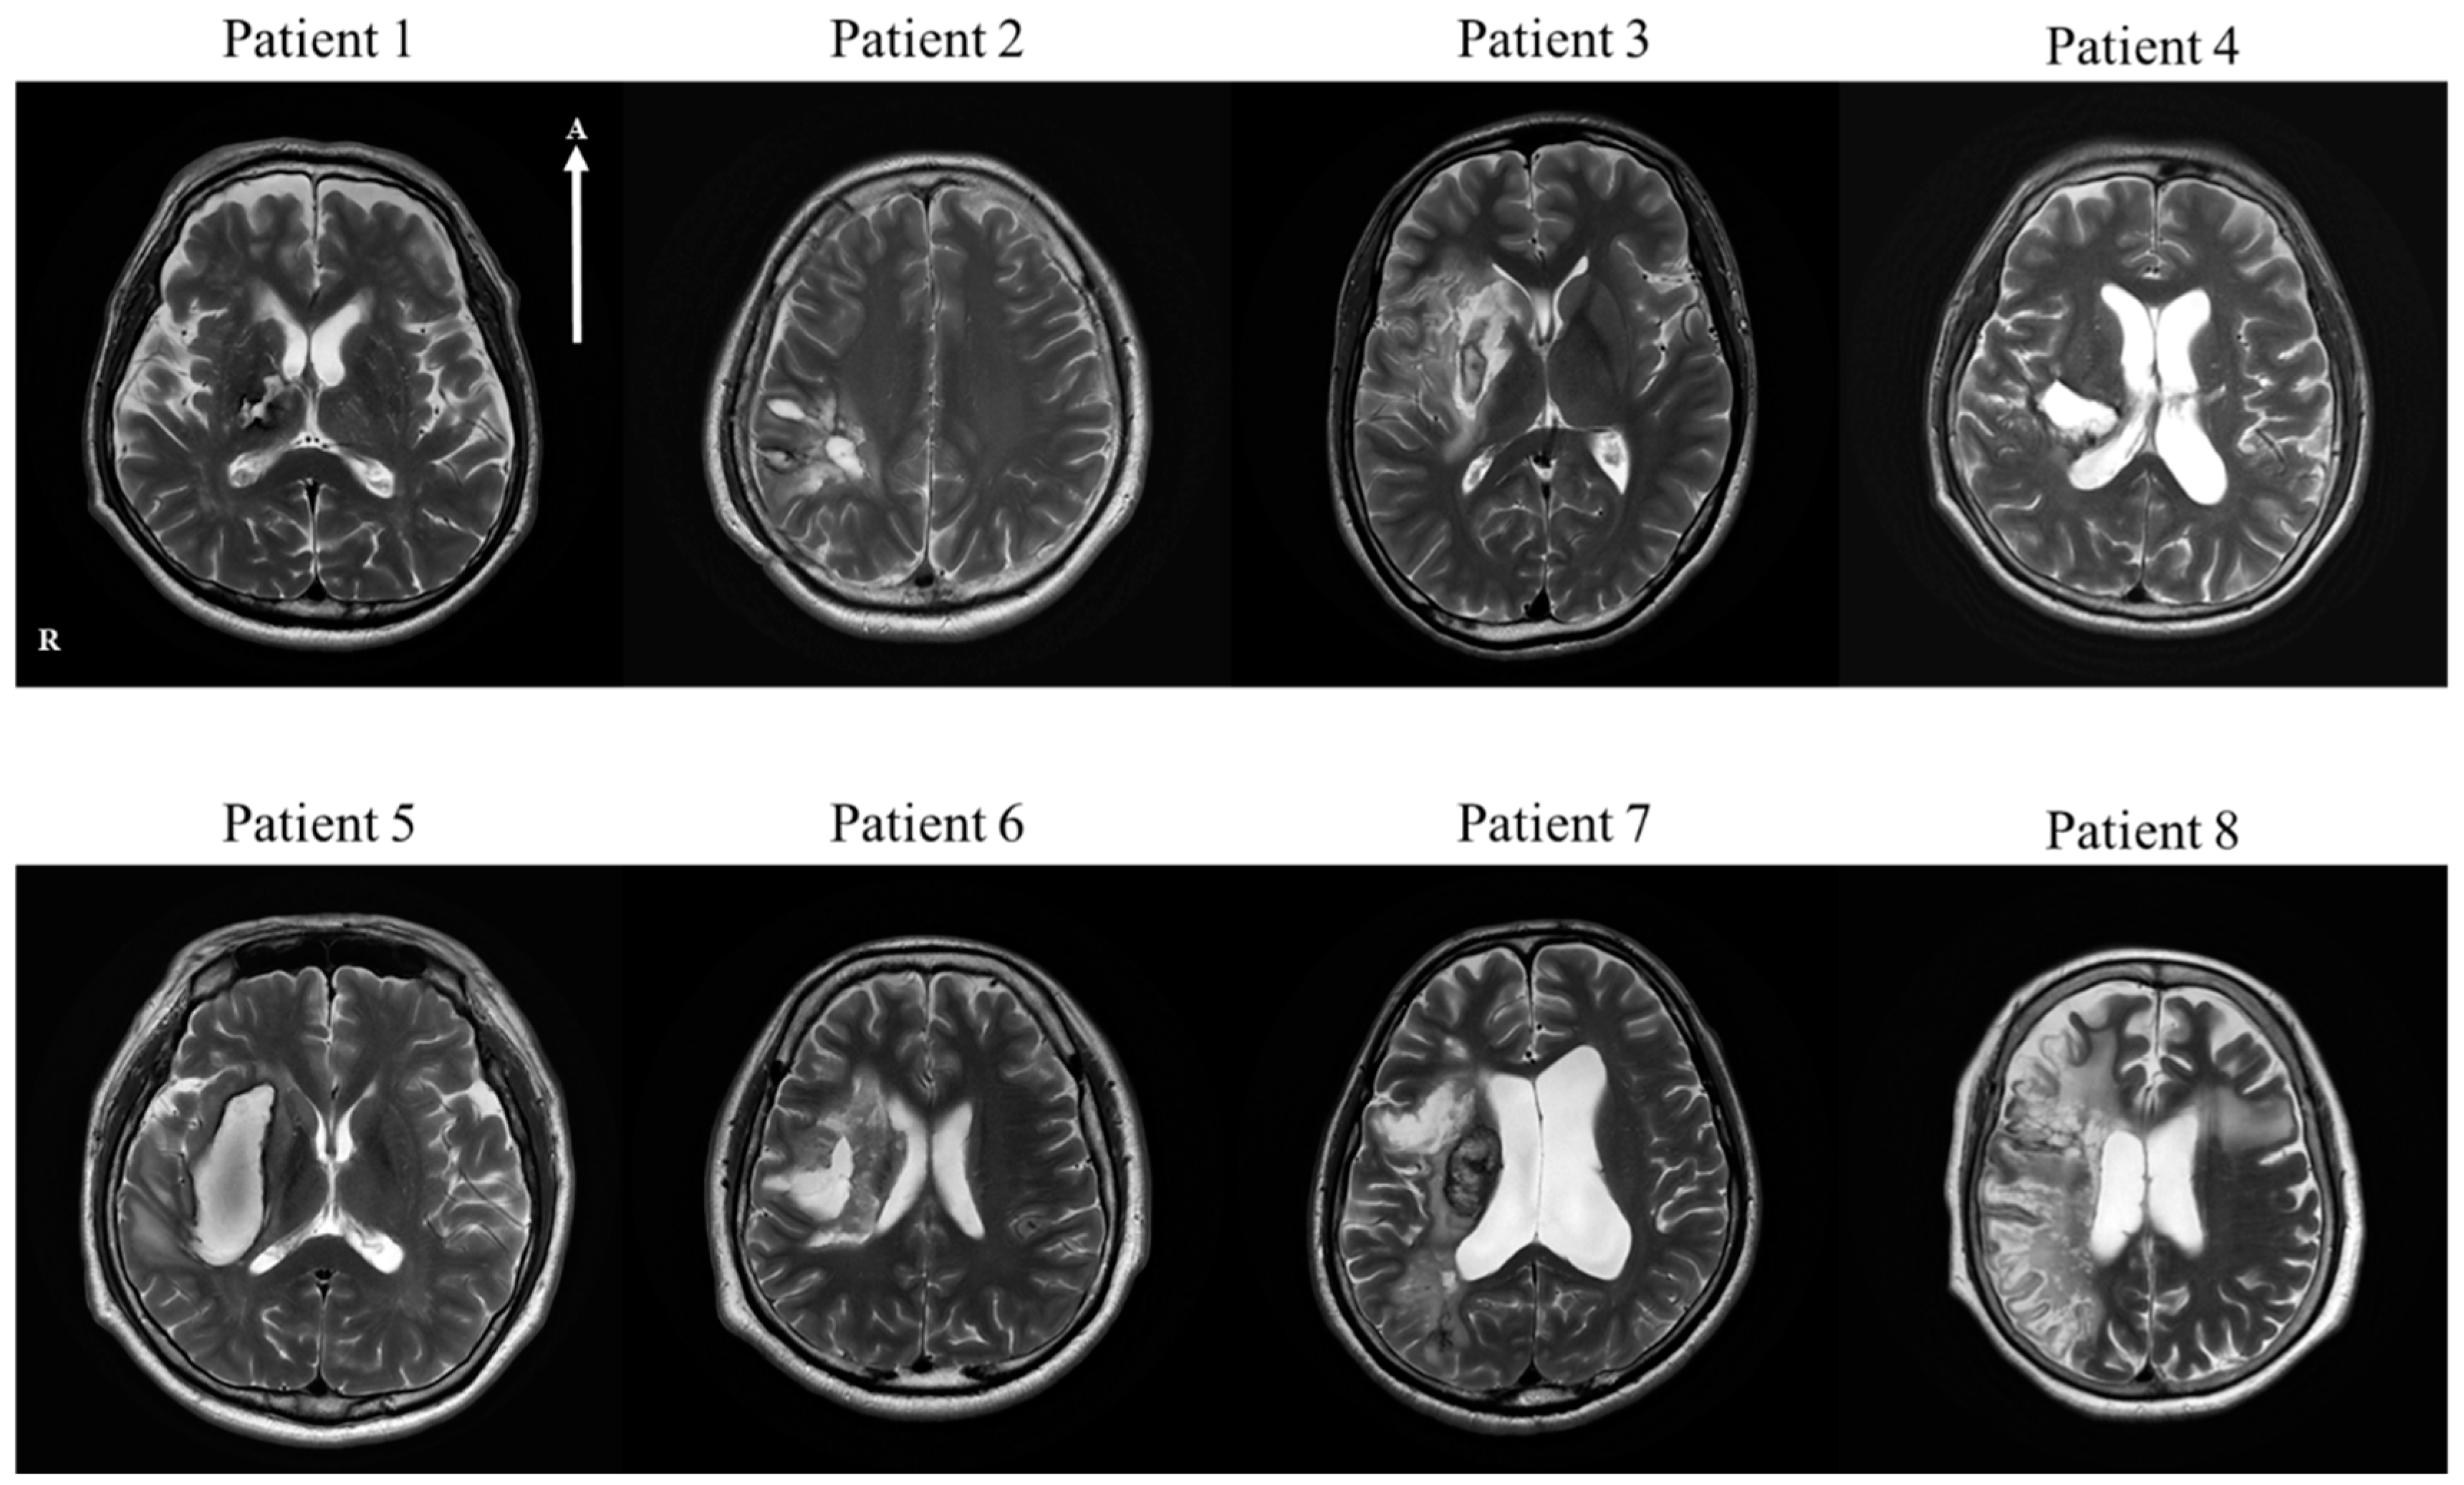

| Patient 1 | 68 | M | Thalamus and posterior limb of internal capsule, right | H | 23 | HTN | Craniotomy | |

| Patient 2 | 37 | M | Parietal lobe, right | H | 30 | Craniectomy and Cranioplasty | ||

| Patient 3 | 23 | M | Frontal lobe, insular cortex and basal ganglia, right | I | 28 | cilotazol, atovastatin | ||

| Patient 4 | 47 | M | Basal ganglia, frontoparietal lobe, right | H | 17 | HTN | Conservative treatment | |

| Patient 5 | 61 | M | Basal ganglia, right | H | 26 | HTN, MI | Conservative treatment | |

| Patient 6 | 48 | M | Basal ganglia, right | H | 28 | Craniotomy | ||

| Patient 7 | 67 | M | Frontal, parietal, temporal lobe and insula, right | I | 26 | Thrombectomy | aspirin, atorvastatin | |

| Patient 8 | 69 | F | Basal ganglia fronto-temporal lobe, right | I | 21 | AF | Thrombectomy | micronized rivaroxaban, atorvastatin |